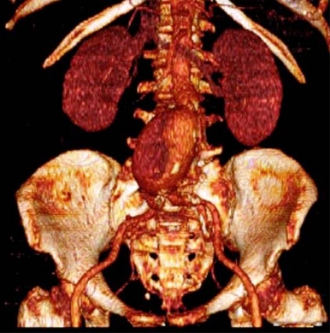

巨大な破裂性遠位弓部大動脈瘤(術前)